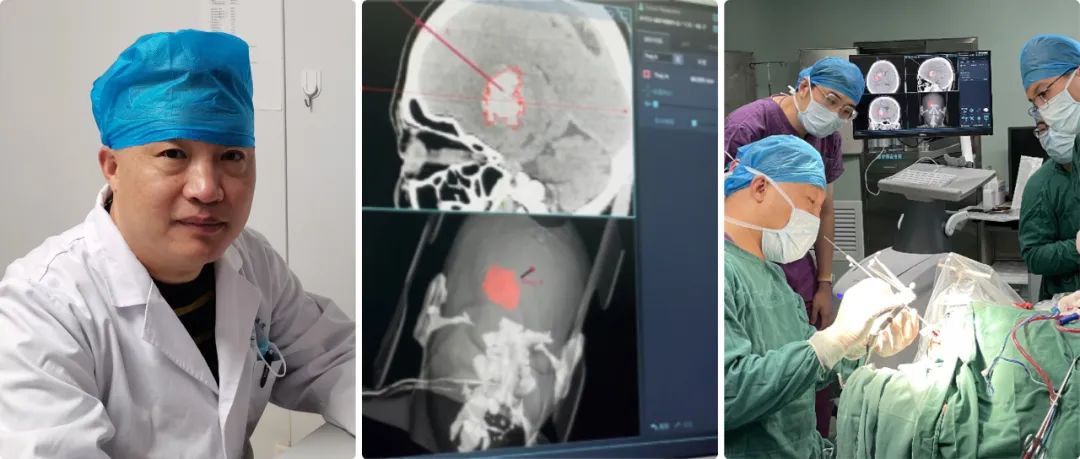

高磊:我院神經(jīng)外科自1998年正式成立,至今經(jīng)過(guò)二十余年的努力,已成為濟(jì)南市濟(jì)陽(yáng)區(qū)人民醫(yī)院發(fā)展最為迅猛的學(xué)科之一??剖议_放床位45張,其中搶救、監(jiān)護(hù)床位5張。年門診量5000余人次,年收治患者2600余人次,每年完成各類手術(shù)400余臺(tái),其中危重的病人手術(shù)170-200例左右。

高磊:濟(jì)陽(yáng)區(qū)人口約53萬(wàn)左右,我們是濟(jì)南市黃河以北地區(qū)重型顱腦外傷、出血性腦血管病及其它腦科急癥救治中心,區(qū)內(nèi)腦出血危重癥基本上都到我們醫(yī)院就診;我們治療范圍也輻射了周邊縣/區(qū),但是量不大。

高磊:隨著現(xiàn)在交通法規(guī)的日益完善,現(xiàn)在顱腦創(chuàng)傷的病人正在逐年的減少,自發(fā)性腦出血的病人卻在逐年的增多,所以科室也從單純的顱腦創(chuàng)傷逐步成為集顯微神經(jīng)外科、立體定向神經(jīng)外科、血管內(nèi)介入神經(jīng)外科等多個(gè)亞學(xué)科的綜合性神經(jīng)外科,下一步以腦血管病為主要救治方向。

但是大部分病人雖然是腦出血,但是病人生命體征比較穩(wěn)定,我們盡可能用神經(jīng)導(dǎo)航來(lái)實(shí)現(xiàn)微創(chuàng)血腫穿刺引流。

神經(jīng)導(dǎo)航微創(chuàng)手術(shù)就避免了傳統(tǒng)開顱手術(shù)的弊端,它可以實(shí)現(xiàn)精準(zhǔn)穿刺血腫引流,病人一次性接受手術(shù),恢復(fù)比較快,并對(duì)病人整體創(chuàng)傷很小。

高磊:準(zhǔn)備做神經(jīng)導(dǎo)航手術(shù)之前,我們給患者進(jìn)行顱腦CT薄層掃描,層厚大約在0.625毫米-1毫米,然后在神經(jīng)導(dǎo)航系統(tǒng)進(jìn)行重建,在重建虛擬像上選擇合適的靶點(diǎn)。

靶點(diǎn)選擇的三個(gè)原則:第一,從頭皮到血腫的穿刺路徑比較短;第二,避開大腦重要功能區(qū);第三避開重要的神經(jīng)血管。

我們經(jīng)過(guò)對(duì)病人注冊(cè),實(shí)現(xiàn)在電腦上與實(shí)際人頭部位置融合,再根據(jù)電腦上確定的穿刺位置,選擇實(shí)際病人顱上的穿刺位置,兩者基本上重合,這樣確保穿刺路徑的精準(zhǔn)性。

高磊:華科精準(zhǔn)這款Sinovation神經(jīng)導(dǎo)航系統(tǒng)功能比較完善/強(qiáng)大的,顱腦CT、核磁共振、血管造影等都能實(shí)現(xiàn)圖像的重建。

高磊:任何手術(shù)設(shè)備,尤其導(dǎo)航系統(tǒng),漂移不可避免;Sinovation神經(jīng)導(dǎo)系統(tǒng)的誤差可以控制在0.5毫米左右。

我們對(duì)腦組織等漂移怎么克服呢?第一精準(zhǔn)定位,第二實(shí)時(shí)導(dǎo)航,就是穿刺點(diǎn)確定后,我們通過(guò)顱骨鉆孔到達(dá)皮層,再進(jìn)行一次注冊(cè)和校正偏差,確保漂移減到最小的程度。

自從引進(jìn)導(dǎo)航系統(tǒng),我們科室技術(shù)水平得到了大幅的提升,正如剛才所講沒有導(dǎo)航之前,我們腦出血都是手術(shù)開顱,徒手穿刺誤差比較大,穿刺效果也比較差,有時(shí)病人的病程住院時(shí)間延長(zhǎng)了,而且效果也不好。

現(xiàn)在我們有了導(dǎo)航,穿刺技術(shù)可以說(shuō)得到了質(zhì)的飛躍;在導(dǎo)航輔助下,基本上可以說(shuō)穿刺百發(fā)百中,病人術(shù)后恢復(fù)也非???,功能改善也非常顯著,科室技術(shù)水平得到了飛躍式的提升,區(qū)域及周邊病人的社會(huì)評(píng)價(jià)也反響很好。